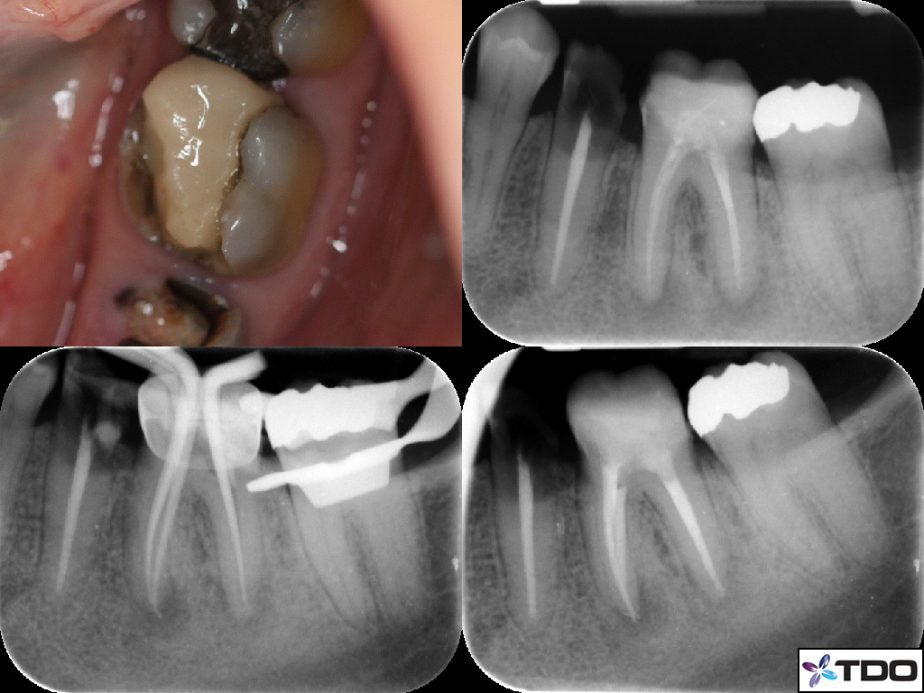

Orthograde Endodontic Retreatment With Composite Core

Patient E presented with a broken down tooth 36. The tooth had been previously endodontically treated several years prior, and the tooth restored with composite resin. Over the years, the patient developed secondary caries and breakdown of tooth 36. She wanted to rehabiltaite her teeth, and her referring dentist requested that the tooth 36 be retreated and a core placed. Orthograde endodontic retreatment was performed for the tooth over two visits with calcium hydroxide dressing.

At the first visit, the tooth was accessed and old gutta-percha remnants removed using retreatment files D1, D2, D3. The shaping of the three canals was achieved with ProTaper Next instrumentation X1, X2.

Three weeks after debridement was completed Patient E was a The tooth was obturated with gutta-percha and AH Plus sealer.

A composite resin restoration core was placed. An orthodontic band was utilised as a matrix for the composite buildup.